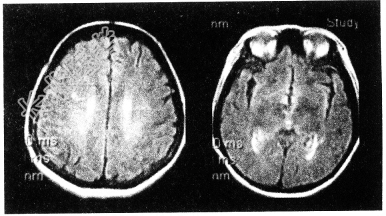

- [材料题] 女性,48岁。渐进性肢体无力半年。MRI所示如下图。

- 多项选择题1.根据MRI表现,可能的诊断是

A、多发脑缺血

B、多发性硬化

C、脑白质稀疏

D、脑萎缩

E、脑炎

F、脑白质病变